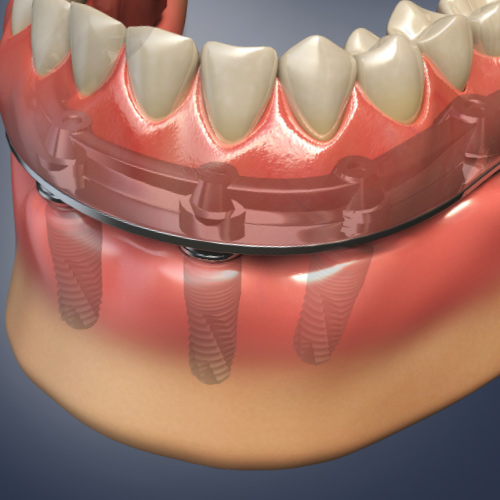

Dental Rehabilitation of the Atrophic Maxilla

Ankur Johri, DDS, MD, FACS

Friday, July 29, 2022

This Compendium eBook features a continuing education (CE) article presents important diagnostic and treatment planning principles of the All-on-4 treatment concept for the rehabilitation of the atrophic maxillary arch, and includes a case report illustrating free-hand implant placement using this treatment approach.